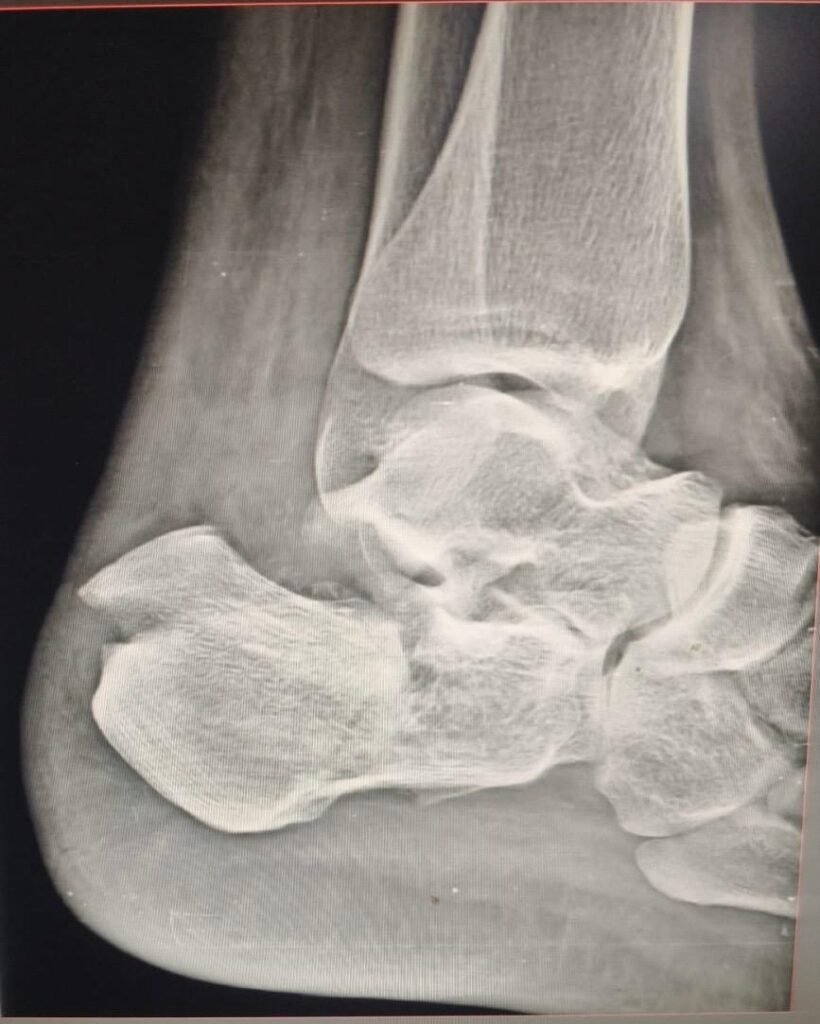

Minimal invasive calcaneum fracture surgery                                </p>

Minimal invasive calcaneum fracture surgery

Minimal invasive calcaneum surgery repairs heel fractures with small cuts, less pain, and quicker recovery.